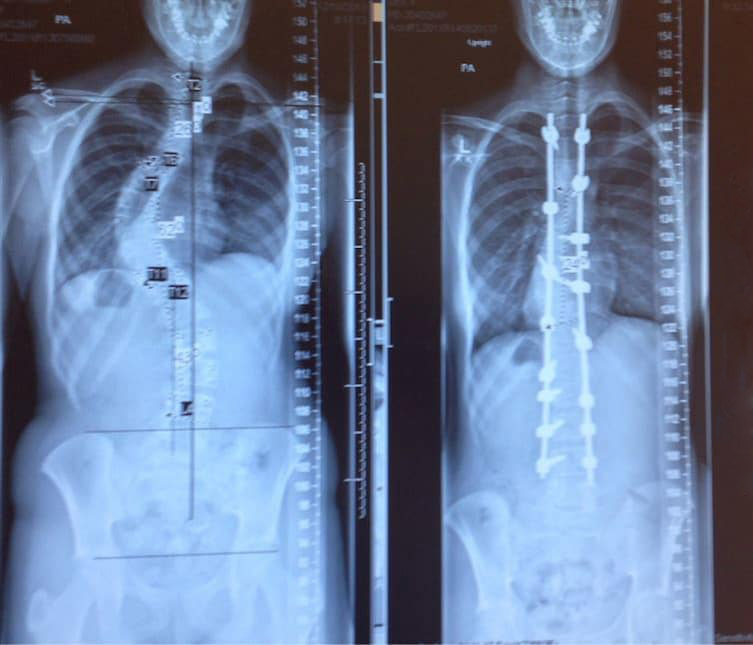

14. RÖNTGENKÉP GERINCFERDÜLÉS (SCOLIOSIS) KEZELÉS ELŐTT ÉS UTÁN